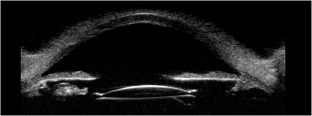

The trans-scleral four-point fixation technique was introduced to provide a stable lens fixation in patients with inadequate capsular support. This technique most commonly uses Akreos-AO or Micropure lenses with a Gore-Tex suture. This study aimed to report long term outcomes and complications of this technique.

106 patients were included (median age 63 (17–83)). Indications were IOL complications (69/106, 65%); aphakia (18/106, 17%); or subluxed crystalline lens (19/106, 18%). Median follow-up was 77 weeks (range 10–200). Median postoperative BCVA was 0.3 LogMAR (IQR 0.2–0.6) at final visit with a median improvement of 0.4 LogMAR. The median postoperative spherical equivalent was −0.25 dioptres(D), with −1.75D astigmatism. Postoperative complications included cystoid macular oedema (8.5%), endophthalmitis (1.8%) and suture issues, including re-threading (1.8%), conjunctival resuturing (1%) or knot repositioning (4%). 10 patients had pre-existing corneal pathology and subsequently had a planned corneal graft.

Gore-Tex fixated IOLs provide good visual improvement with long-term IOL stability. This series reports all patients who underwent the surgery including those performed during the learning curve and training, showing real-world outcomes.